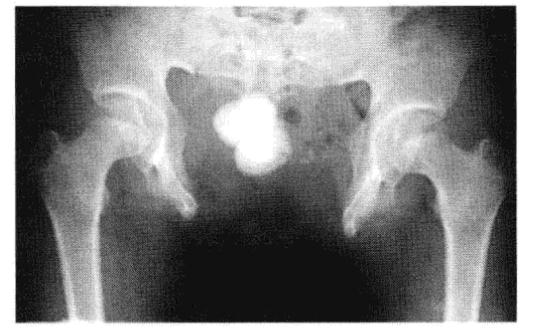

核心提示:骨盆骨折是一种严重外伤,占骨折总数的1%~3%,多由高能外伤所致,半数以上伴有合并症或多发伤,致残率高达50%~60%。最严重的是创伤性失血性休克及盆腔脏器合并伤,救治不当有很高的死亡率,可达10.2%。跟着小编去认识一下...

核心提示:耻骨联合分离症,是指骨盆前方两侧耻骨纤维软骨联合处,因外力而发生微小的错移,表现耻骨联合距离增宽或上下错动出现局部疼痛和下肢抬举困难等功能障碍的软组织损伤性疾病。跟着小编去认识一下关于耻骨联合分离的...